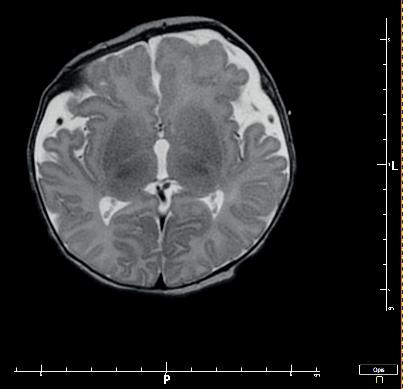

Kolejną interesującą publikacją jest artykuł Studium przypadku zespołu mozaikowej trisomii chromosomu 9 prof. Lidii Perenc z Instytutu Nauk o Zdrowiu Uniwersytetu Rzeszowskiego i współautorów. Zespół mozaiki trisomii 9 został opisany w 1973 roku przez amerykańskiego genetyka R. Haslama; w aktualnych danych uzyskanych z portalu orpha.net zaliczany jest do chorób rzadkich. W artykule omówiono przypadek kliniczny mozaikowej trisomii chromosomu 9 u niemowlęcia płci męskiej. Autorzy wskazują, że dla ustalenia prawidłowego rozpoznania należy uporządkować dane uzyskane na podstawie wywiadu, badania przedmiotowego i badań dodatkowych. W przypadku podejrzenia nieprawidłowego genotypu jako czynnika etiologicznego należy wykonać odpowiednie badania genetyczne. Warto również porównać obraz kliniczny i historię choroby pacjenta z danymi przedstawionymi w literaturze.

Another interesting publication is the article Case study of mosaic trisomy 9 syndrome by Professor Lidia Perenc from the Institute of Health Sciences at the University of Rzeszów and co-authors. Mosaic trisomy 9 syndrome was described in 1973 by American geneticist R. Haslam, and is classified as a rare disease in current data obtained from the orpha. net portal. This article discusses a clinical case of mosaic trisomy 9 in a male infant. The authors point out that in order to establish a correct diagnosis, the data obtained from the history, physical examination and additional investigations should be sorted out. If an abnormal genotype is suspected as an aetiological factor, appropriate genetic tests should be performed. It is also worth comparing the patient’s clinical picture and medical history with data presented in the literature.